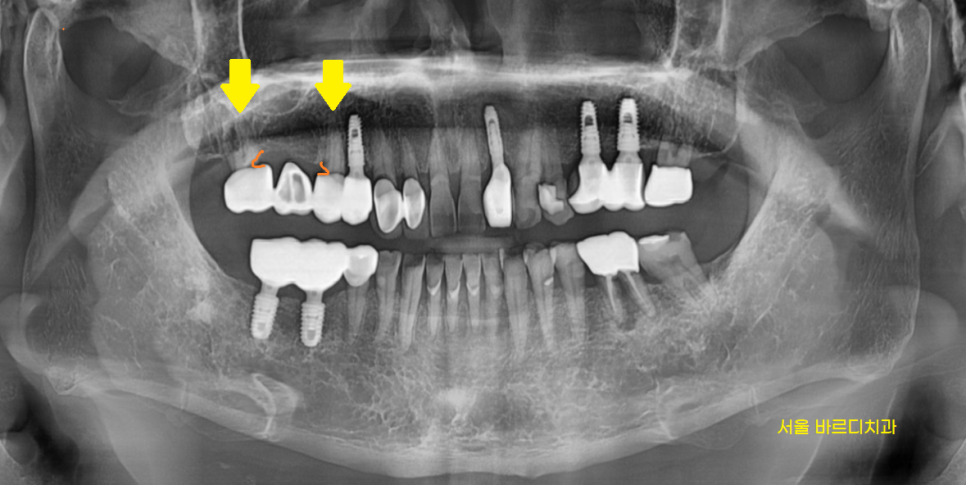

환자분께 설명 드렸던 사진입니다.

동그라미로 표시한 부위가 충치입니다.

단순히 충치만 있는 것이 아니라

한쪽 뿌리 뼈도 많이 녹아

검정색으로 보이네요~